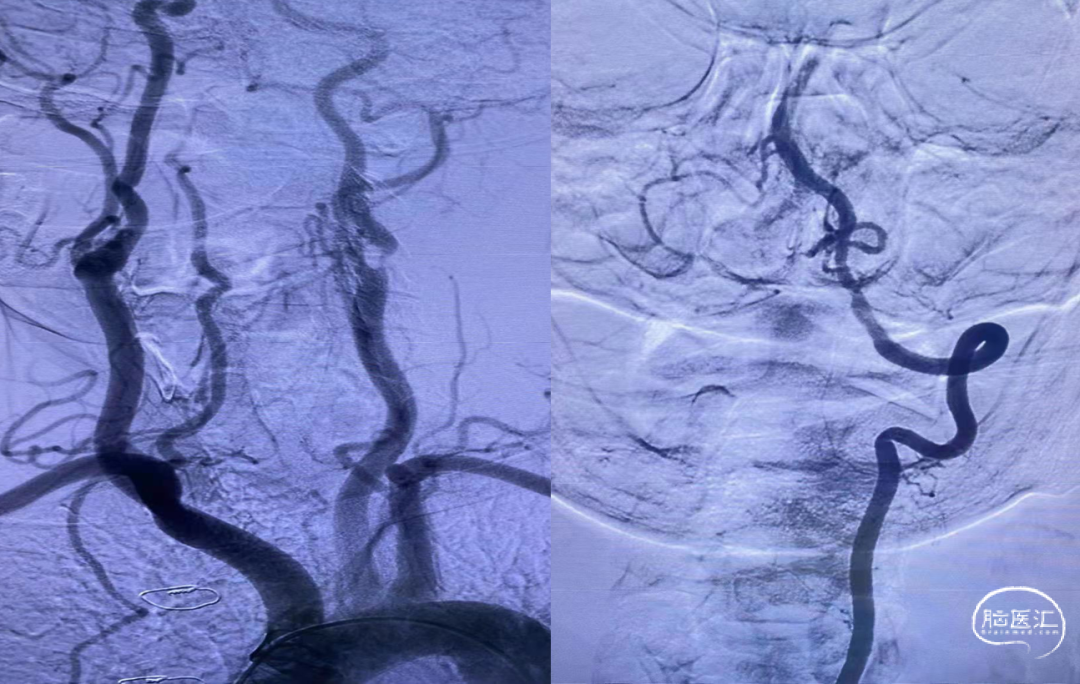

脑血管造影提示:左侧颈内动脉起始段重度狭窄,基底动脉尖闭塞,栓塞可能性大

持续保持负压约2分钟后,持续负压抽吸下缓慢撤出抽吸导管,撤出抽吸导管过程中出现回血通畅。手推造影,见基底动脉显影良好,双侧大脑后动脉显影良好,双侧小脑上动脉显影良好,TICI 分级3级。